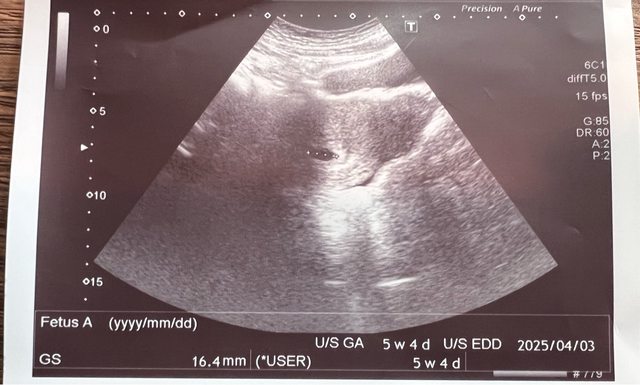

最後一次月經來是6/22 8/5 產檢看醫生 顯示胚囊5w+4d https://i.imgur.com/Ab9QSb4.jpeg